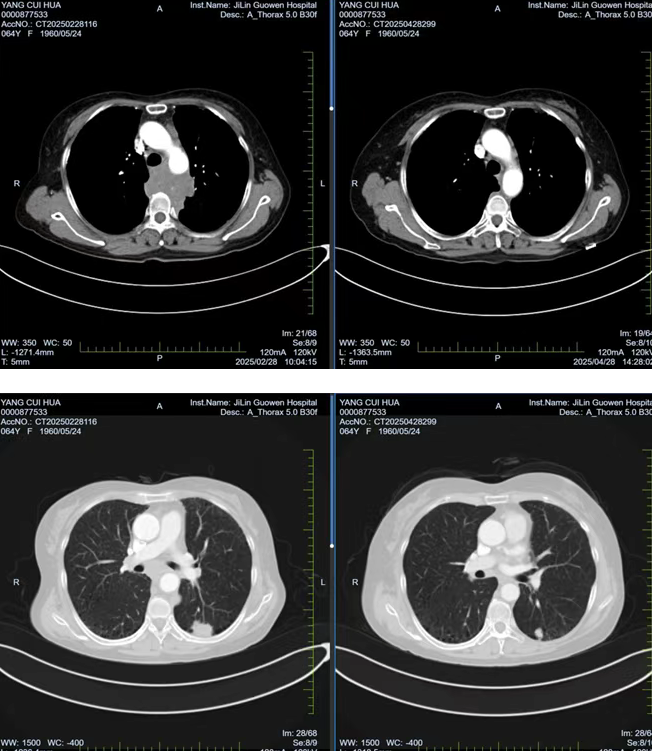

張阿姨因胸背部疼痛持續(xù) 1個(gè)月且逐漸加重,在當(dāng)?shù)蒯t(yī)院檢查時(shí)發(fā)現(xiàn)左肺存在腫物,初步考慮為惡性腫瘤。經(jīng)熟人介紹,了解到我院在腫瘤專(zhuān)科疾病治療方面的優(yōu)勢(shì)后,該患者前往我院就診。胸部腫瘤放化療二科為其安排了 PET/CT 檢查,并對(duì)左側(cè)鎖骨上腫大淋巴結(jié)進(jìn)行穿刺活檢,最終明確診斷為左肺下葉高級(jí)別神經(jīng)內(nèi)分泌癌,臨床分期為 cT1cN3M0 IIIb 期,且縱隔轉(zhuǎn)移淋巴結(jié)已侵犯椎體,患者因劇烈疼痛,生活質(zhì)量受到嚴(yán)重影響。

經(jīng)過(guò) 1 周期的免疫聯(lián)合化療后,患者的胸背部疼痛逐漸減輕,目前患者疼痛癥狀已得到改善,生活質(zhì)量得到了顯著提升。